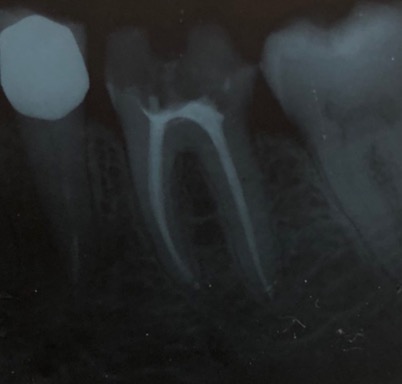

Una corretta terapia canalare con un perfetto sigillo a livello degli apici delle radici è fondamentale. I denti devitalizzati impropriamente possono creare ulteriori problemi che poi andranno a ripercuotersi sulle cure effettuate successivamente come le ricostruzioni e le corone protesiche con conseguente fallimento del piano terapeutico.

Capita spesso di incontrare denti già devitalizzati in maniera impropria che necessitano, seppur asintomatici, di essere ritrattati per evitare che i granulomi infetti visibili radiograficamente si evolvano riassorbendo tutto l’osso sottostante.